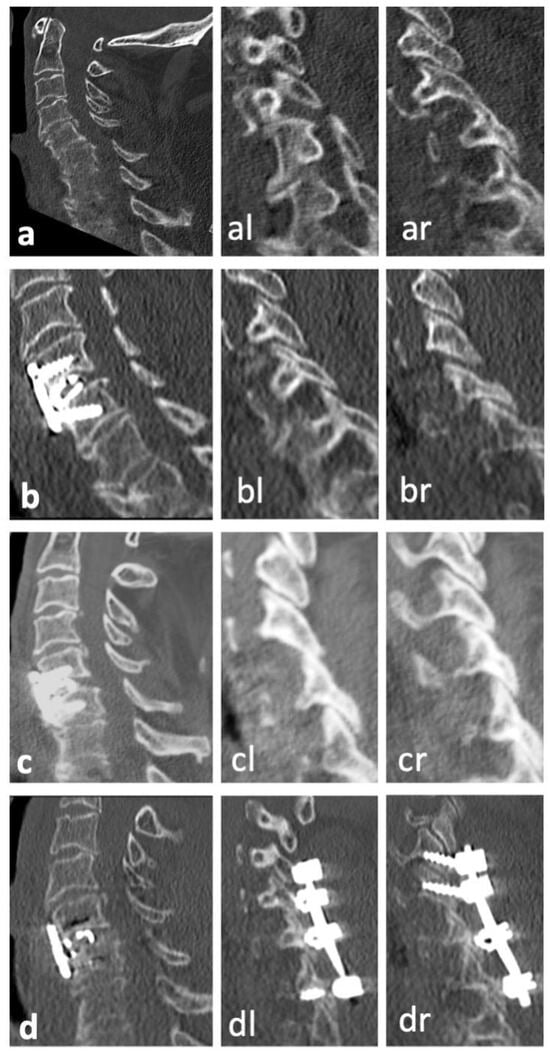

| No | Sex | Age | Level | Injury Type | Primary Treatment | Therapy of Secondary Dislocation |

|---|---|---|---|---|---|---|

| 1 | f | 91 | C6/7 | B2 | ACDF C6/7 with plate and iliac crest graft | Posterior instrumentation C5/6/7/Th1 |

| 2 | f | 74 | C5/6 | B2 | ACDF C5/6 with plate and iliac crest graft | Removal of plate and ACDF C5/6/7 with plate |

| 3 | m | 78 | C6/7 | B3 | Posterior instrumentation C3/4 to C6/7 andAnterior fixation C5 to C7 with plate | Posterior instrumentation C3/4/5/6/7Anterior fixation C5 to C7 with plate |

| 4 | m | 82 | C5/6 | B3 | ACDF C5/6 with plate and iliac crest graft | Posterior instrumentation C3/4/5/6/7 and ACDF C4/5/6/7 with plate and intervertebral cages |

| 5 | m | 66 | C6/7 | B3 | ACDF C5/6/7 with plate and iliac crest grafts | Halo fixator |

| 6 | f | 80 | C6/7 | C | ACDF C6/7 with plate and allogenous bone graft | Posterior instrumentation C4/5 to Th1/2 |

| 7 | f | 70 | C6/7 | C | ACDF C6/7 with plate and iliac crest graft | Posterior instrumentation C3/4/5 to Th1/2 |

| 8 | m | 68 | C6/7 | C | ACDF C6/7 with plate and iliac crest graft | Posterior instrumentation C6/7/Th1/2 |

| 9 | f | 74 | C6/7 | C | ACDF C5/6/7 with plate and intervertebral cages | Posterior instrumentation C5/6/7/Th1 |

| 10 | m | 79 | C6/7 | C | ACDF C6/7 with plate and iliac crest graft | Posterior instrumentation recommended; patient refused |

| 11 | f | 67 | C5/6 | C | ACDF C5/6 with plate and intervertebral cage | Posterior instrumentation C4/5/6/7 |